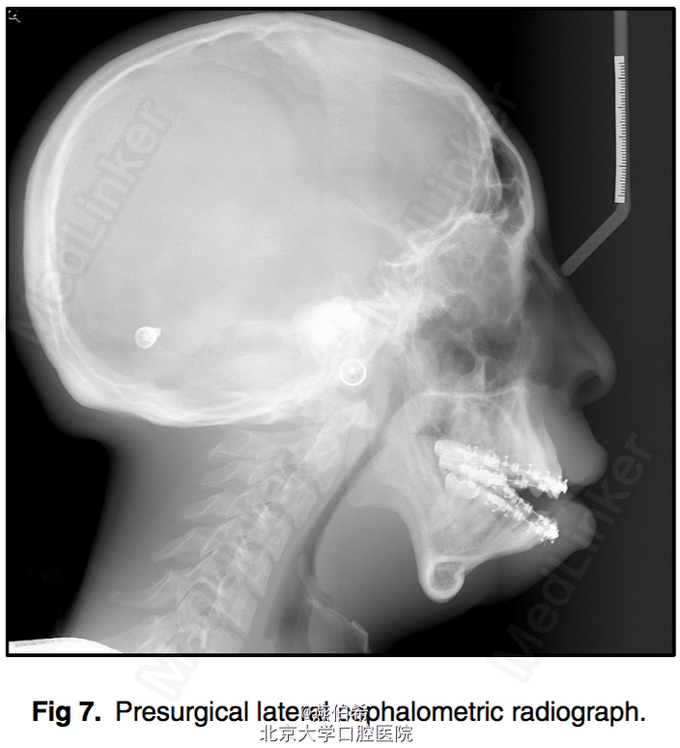

Treacher Collins综合征 扩弓解决宽度不调,拔4个4矫正牙量骨量不调, 后行口外反L行截骨术矫正颌骨问题

术后效果良好。 Treacher Collins 综合征,下颌-面骨发育不全 患病率为每50,000活婴儿中有1个 其表现为颧弓发育不全(81%),小颌畸形(78%)以及由于外耳道闭锁引起的外耳形态异常,同时可能听小骨确实引起的传导性耳聋。 口腔内的表现为高腭穹窿,唇裂,腭裂,牙釉质发育不良,及骨骼导致的前牙开牙合。前磨牙不萌出和上磨牙异位萌出也很常见。 (AJODO,November 2014 Vol 146 Issue 5)